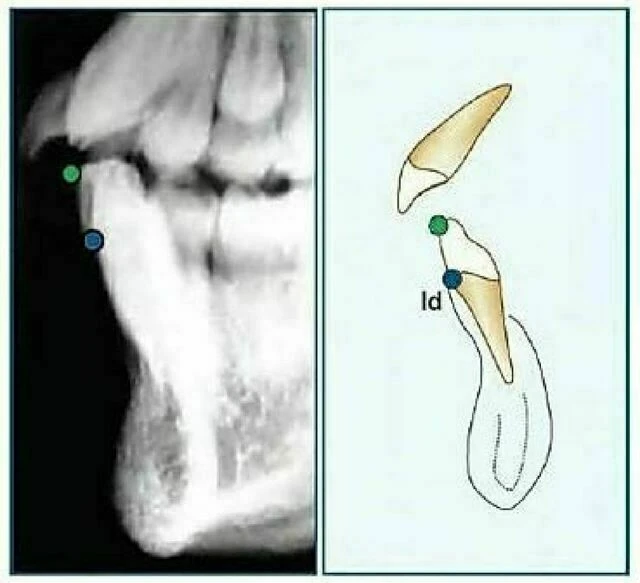

Infradentale (Id): Điểm nằm ở vị trí trên trước nhất của xương ổ răng hàm dưới, thường tìm thấy gần đường nối xi măng – men răng của răng cửa giữa hàm dưới. Còn được gọi là điểm Inferior Prosthion.

Supramentale (điểm “B”): Là điểm nằm ở vị trí sau nhất ở đường cong xương hàm dưới nối từ Infradentale đến Pogonion. Điểm “B” thường tìm thấy gần 1/3 chóp các chân răng cửa hàm dưới và có thể bị che khuất trong suốt quá trình các răng này mọc. Khi nét mặt nhìn nghiêng vùng cằm không lõm thì không thể xác định được điểm “B”.